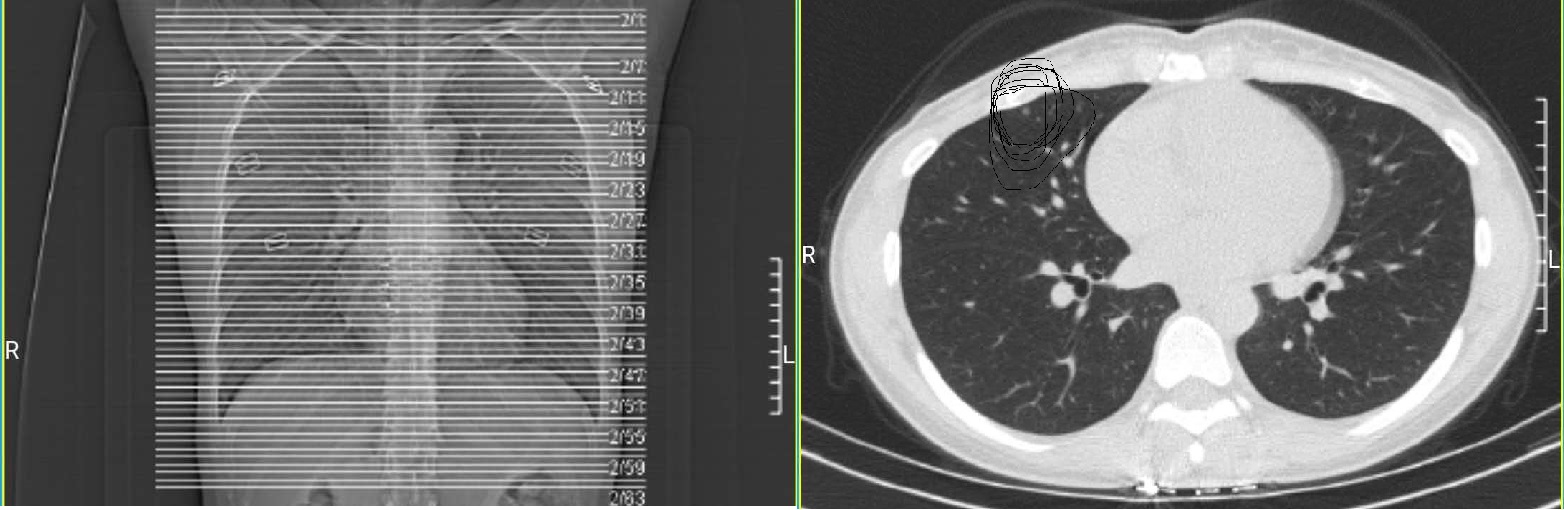

胸片是通过机器发出X射线穿透人体之后被探测器捕捉,并得到了一副透视胸部的平面图像。而CT是多层螺旋扫描,把脏器的分层扫描得出多副图像(分多少层,就能得到多少副图像)。CT扫描的好处在于不仅可以分层检查脏器,还可以通过不同的角度旋转三维重建观察病灶特征。而拍片是平面图,达不到CT的三维效果及病灶的准确位置。例如下图胸片以及胸部CT,其中胸片中专门画出来很多横线,代表CT切的每个层面。

同理胸片,一个平面的扫描透视片中,不仅涵盖肺组织,还包含肋骨等。与肋骨前后重叠的肺组织中的结节灶非常容易被漏诊。此外,胸片容易漏诊心脏影后面的病灶:上面胸片CT对比图中,左边胸片中间梨形白色的影子为心脏影,他有一部分与肺前后重叠。也就是说一个平面透视时,有一部分肺组织是被心脏挡住的。因此心影后面肺部病灶胸片很容易漏诊,而CT就不用担心这个问题。其他还有肺门部位因为血管非常丰富,所以肺部部位的阴影往往因为与血管混杂一起而漏诊。